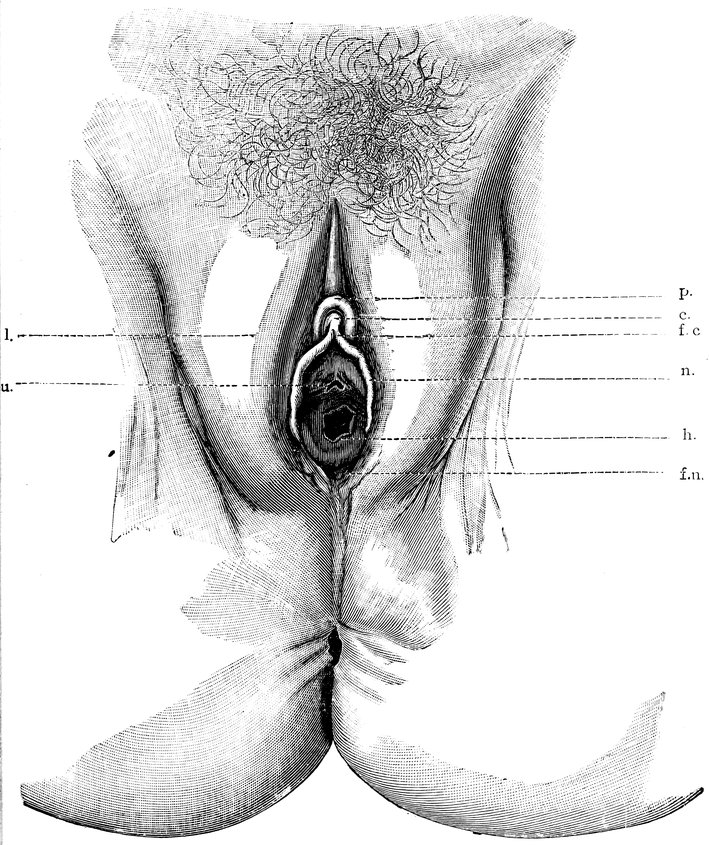

| 12. | Female external genital organs of a virgin | 54 |

| 13. | The external genital organs of a virgin | 55 |

| 48. | The female pudendum, or vulva, with the labia majora | 204 |

| 49. | Vestibule of the vagina, with the labia minora or nymphæ, etc | 205 |